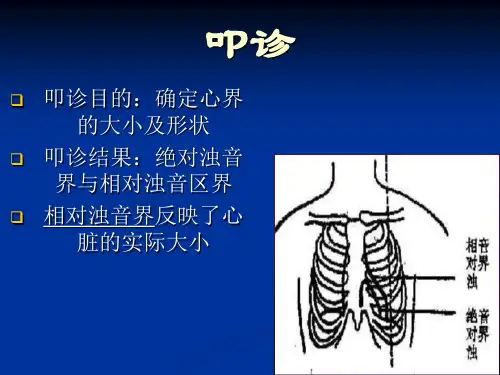

心脏叩诊检查的目的是:确定心界,判定心脏大小、形状及其在胸腔内的位置。

心脏为不含气器官,其不被肺遮盖的部分,叩诊呈绝对浊音(实音)。

而心左右缘被肺遮盖的部分叩诊呈相对浊音。

叩心界是指叩诊心相对浊音界,因为相对浊音界反映心脏的实际大小,具有重要的实用价值。

(二)正常心界(normal cardiac boundary)指心脏的左右相对浊音界。

即心脏在胸部表面的投影。

正常人右心界几乎与胸骨右缘相合,在第4肋间处可在胸骨右缘稍外方;左界第2肋间几乎与胸骨左缘相合,其下方则逐渐左移,并继续向左下形成向外突起的弧形。